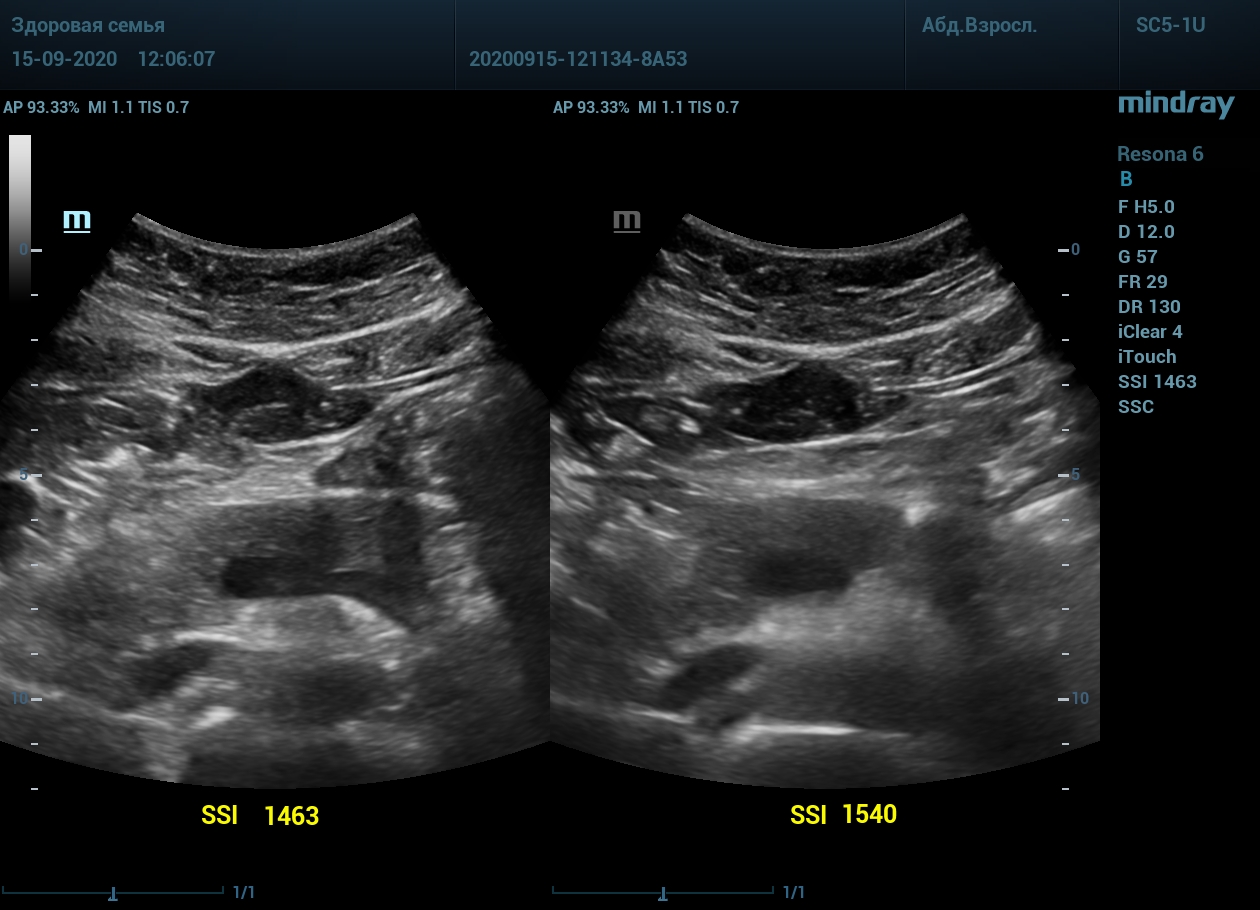

Примеры изображений:

1. Пациент с метеоризмом и большой массой тела. Визуализация поджелудочной железы до и после калибровки скорости ультразвука. Контуры головы и тела железы видны гораздо лучше.